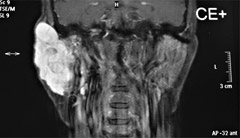

3) 聴神経腫瘍の診断と治療

3) 中頭蓋窩法による聴神経腫瘍摘出術

臨床では自家移植による再建を必要とする頭頸部悪性腫瘍手術、内視鏡下鼻副鼻腔手術、聴力改善手術、頭蓋底外科手術、音声機能改善手術、口蓋扁桃摘出手術に至るまで、耳鼻咽喉科・頭頸部外科の手術をすべて行っております。頭頸部腫瘍・癌の治療に関しは、最高レベルの成績をあげ、頭頸部癌の治療成績の向上に積極的に努めています。